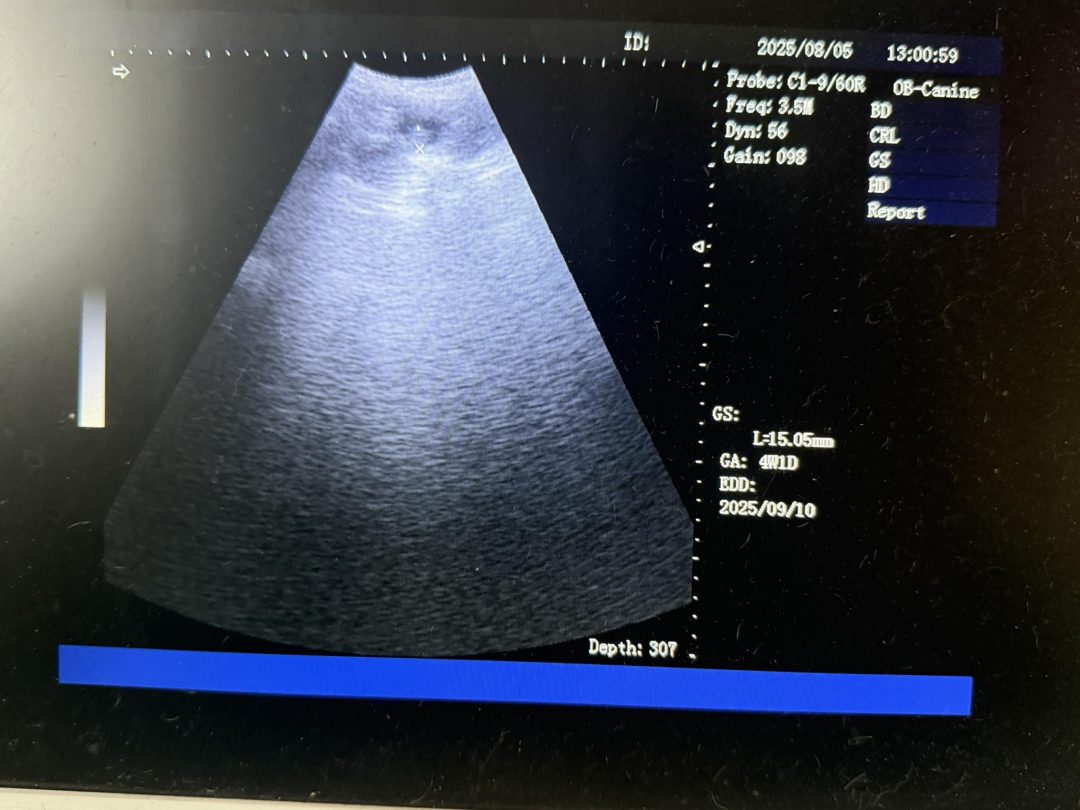

Confirmation ultrasound scan carried out today on a mobile visit in Blackburn

Happy owner when I announced she was expecting babies